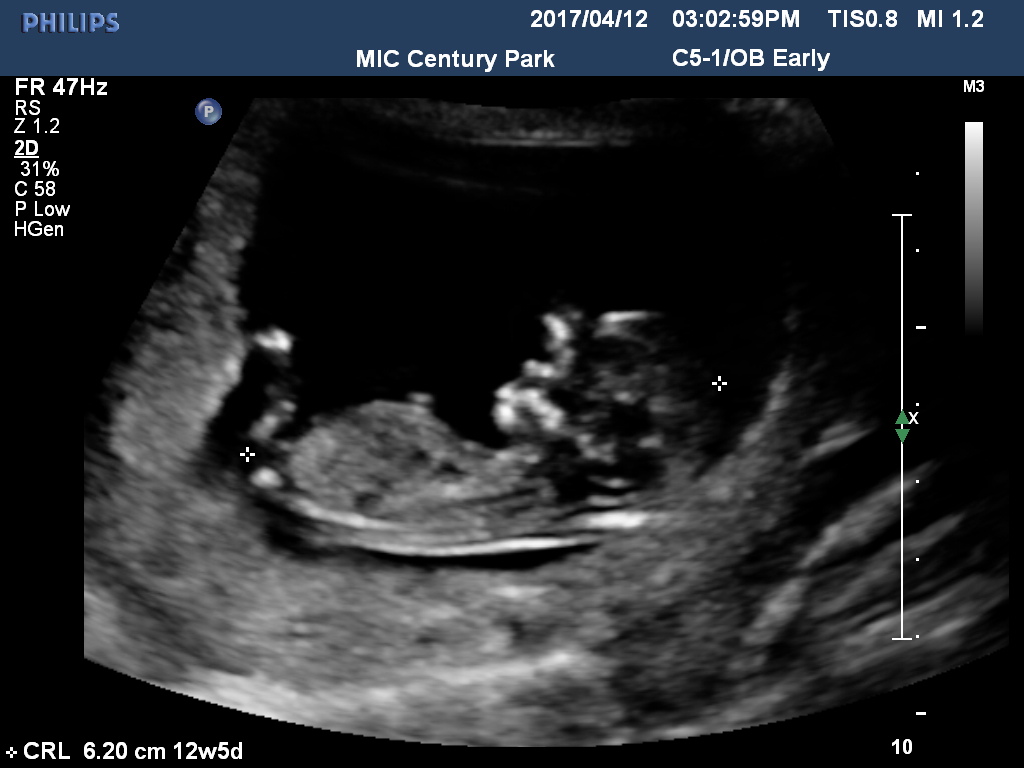

Any ideas if it's a girl or boy nub? I don't even see the nub at all...?

Tricky, maybe boy. Any more pics or a video?

I am leaning boy if I am seeing the nub. Tricky one!

Boy, but not the clearest of shots